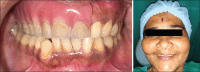

Patient concerns: Issues related to problems associated with resection following mucormycosis, such as occlusal function, aesthetics and facial asymmetry.

Outcome: Positive clinical outcomes, including improved facial symmetry, function and psychological well being with immediate replacement of the teeth, the benefits of which far outweigh the traditional approach.